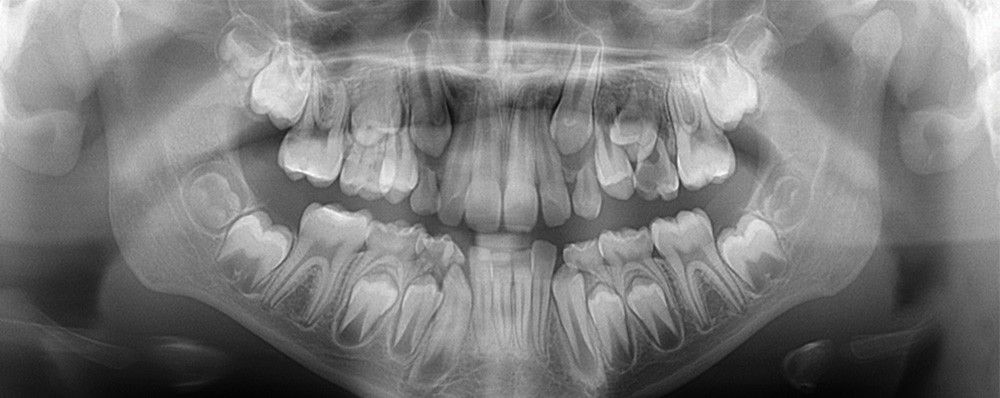

Стоматологические Исследования: Рентген Инвагинации Зубов